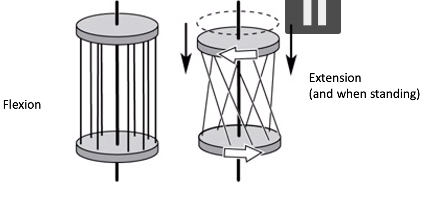

when the hip is extended, what happens to the ligament fibres? [1]

what does this do the the femur & acetabulum? [1]

when the hip is extended, what happens to the ligament fibres? [1]

- fibres become twisted and extended (& tighten)

what does this do the the femur & acetabulum? [1]

ligaments pull head of femur & acetabulum closer